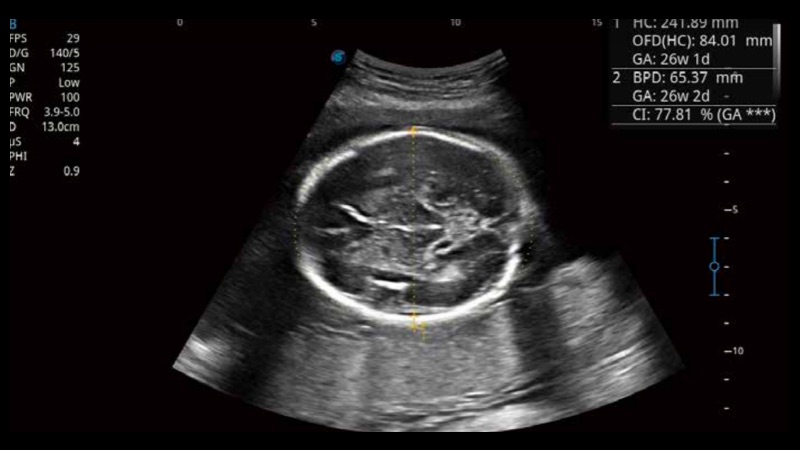

S-Fetus基于大数据深度学习算法,能够帮助您在产前筛查过程中智能识别胎儿标准切面、自动测量并录入报告。一个按键,即可智能、精准、高效地获取胎儿生理指标,极大简化您的产科检查操作。

可快速对产科扫查切面完成胎儿生理学参数的自动测量,减少操作者按键次数,大幅提升检查效率。